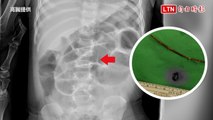

27歲蕭姓女子近日出現喉嚨痛、發燒等症狀,以為只是感冒,沒想到雙手雙腳開始冒出密密麻麻的紅疹,嚇得趕緊就醫,結果竟是感染腸病毒。衛福部彰化醫院小兒科主任馬瑞杉指出,腸病毒不只孩童會感染,大人也法無法倖免,亦有併發重症的可能,至今還在大流行,不管大人小孩都不能輕忽。